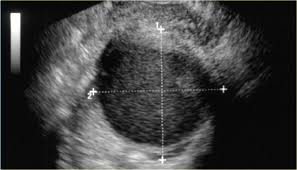

What Does Ovarian Cancer Look Like / What are the Signs & Symptoms? - National Ovarian Cancer ... - Wednesday 25 february is ovarian cancer awareness day. . Most ovarian cysts go away with time. This type of cancer can occur in women who still have their ovaries, but it is of more concern for women who have had their ovaries removed to. What does ovarian cancer look like on an ultrasound? Like ovarian cancer, ppc tends to spread along the surfaces of the pelvis and abdomen, so it is often difficult to tell exactly where the cancer first started. I'm sharing my story in the hope of raising awareness about this devastating disease, and to help raise funds for important australian medical research currently being. Department of health and human services national institutes of it is the most common type of ovarian cancer. What does ovarian cancer look like on an ultrasound? Ovarian cancer is highly curable if it's diagnosed and treated early, but the symptom...